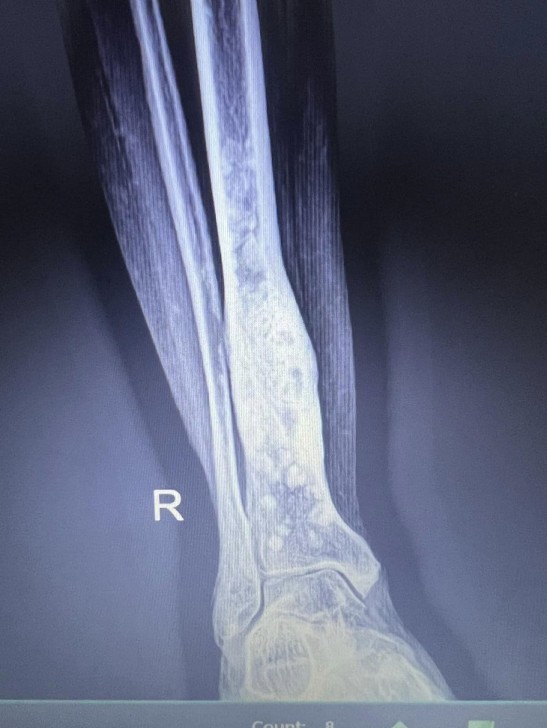

AFN.az xəbər verir ki, tanınmış həkim Aydın Əliyev bu sahədə vəziyyətin getdikcə ağırlaşdığını bildirib. O, xəstələrdən birinin müayinə nəticələrini paylaşaraq bunları yazıb: “Onkoloji xəstəliklərin müayinə və müalicəsinin hələ də icbari tibbi sığorta tərəfindən qarşılanmamasının daha bir qurbanı. Sağ qamış sümüyündəki törəmənin maddi imkansızlıq səbəbindən vaxtında və sistemli müalicə və ya əməliyyat edilməməsi səbəbindən fəqərələrə, qabırğalara, kürək, çanaq sümüklərinə, ağciyərə çoxsaylı metastazları. Demək olar ki, adam həyatını itirib”.